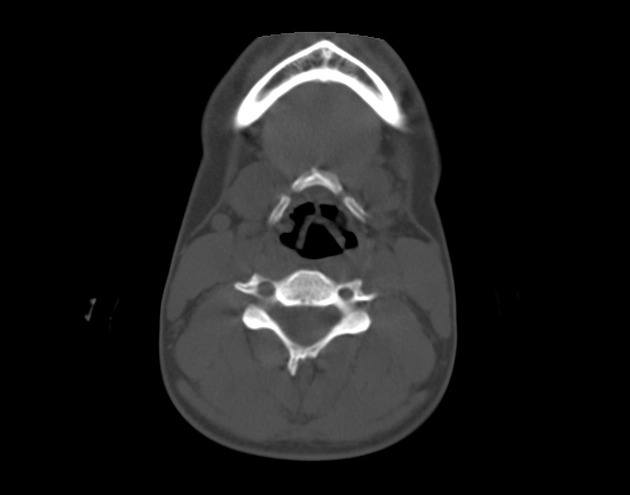

Gãy xương móng

» Thông tin: Nữ giới – 17 tuổi.

» Lâm sàng: Chấn thương vùng cổ.